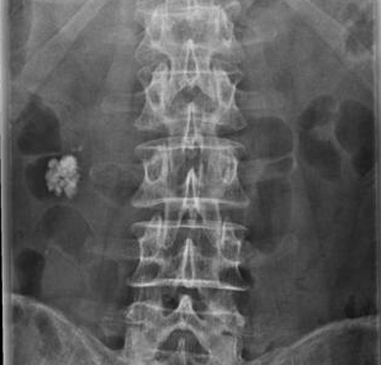

Image une calcul de la

vesicule biliaire situe a hypochondre droit

multilobulaire et a bord lisse . Cliche de face ASP

. |

Mene cas en ASP

de profile droit . Image du calcul situe

avant du corp vertebrale L3 |